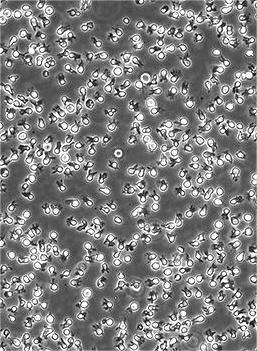

SU-DHL-4

培养方法

90%RPMI-1640+10% FBS

Temperature: 37°C ; Carbon dioxide (CO₂), 5%

悬浮细胞

90% FBS(优质) + 10% DMSO;存于液氮中